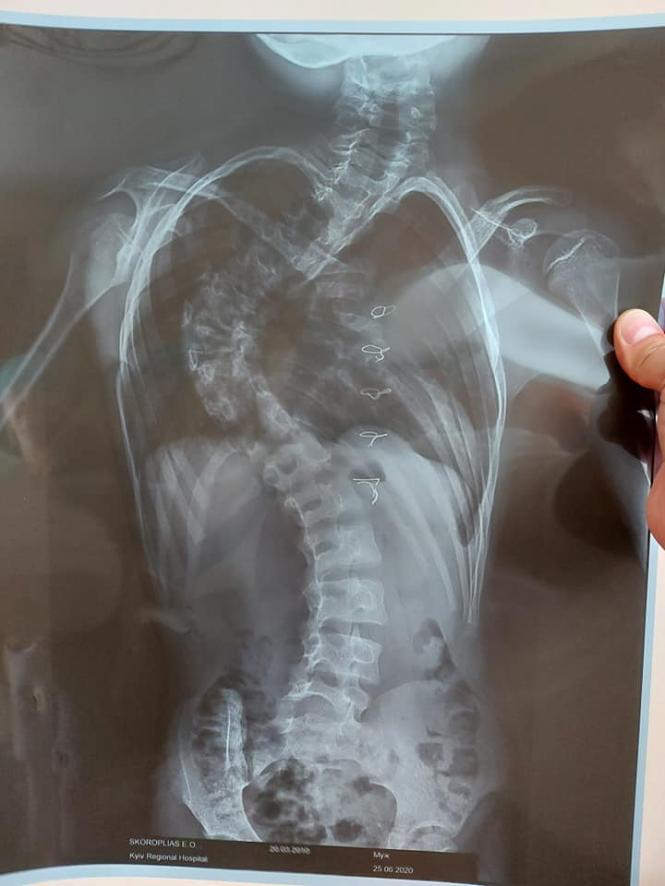

- У Едіка є ще один діагноз - сколіоз. І якщо йому впродовж місяця не зробити операцію, він зовсім не зможе ходити.

Дігноз - сколіоз

Діагноз хлопчика - сколіоз. Він вже дав низку негативних змін на весь організм хлопчика. Тож реабілітація буде тривалою.